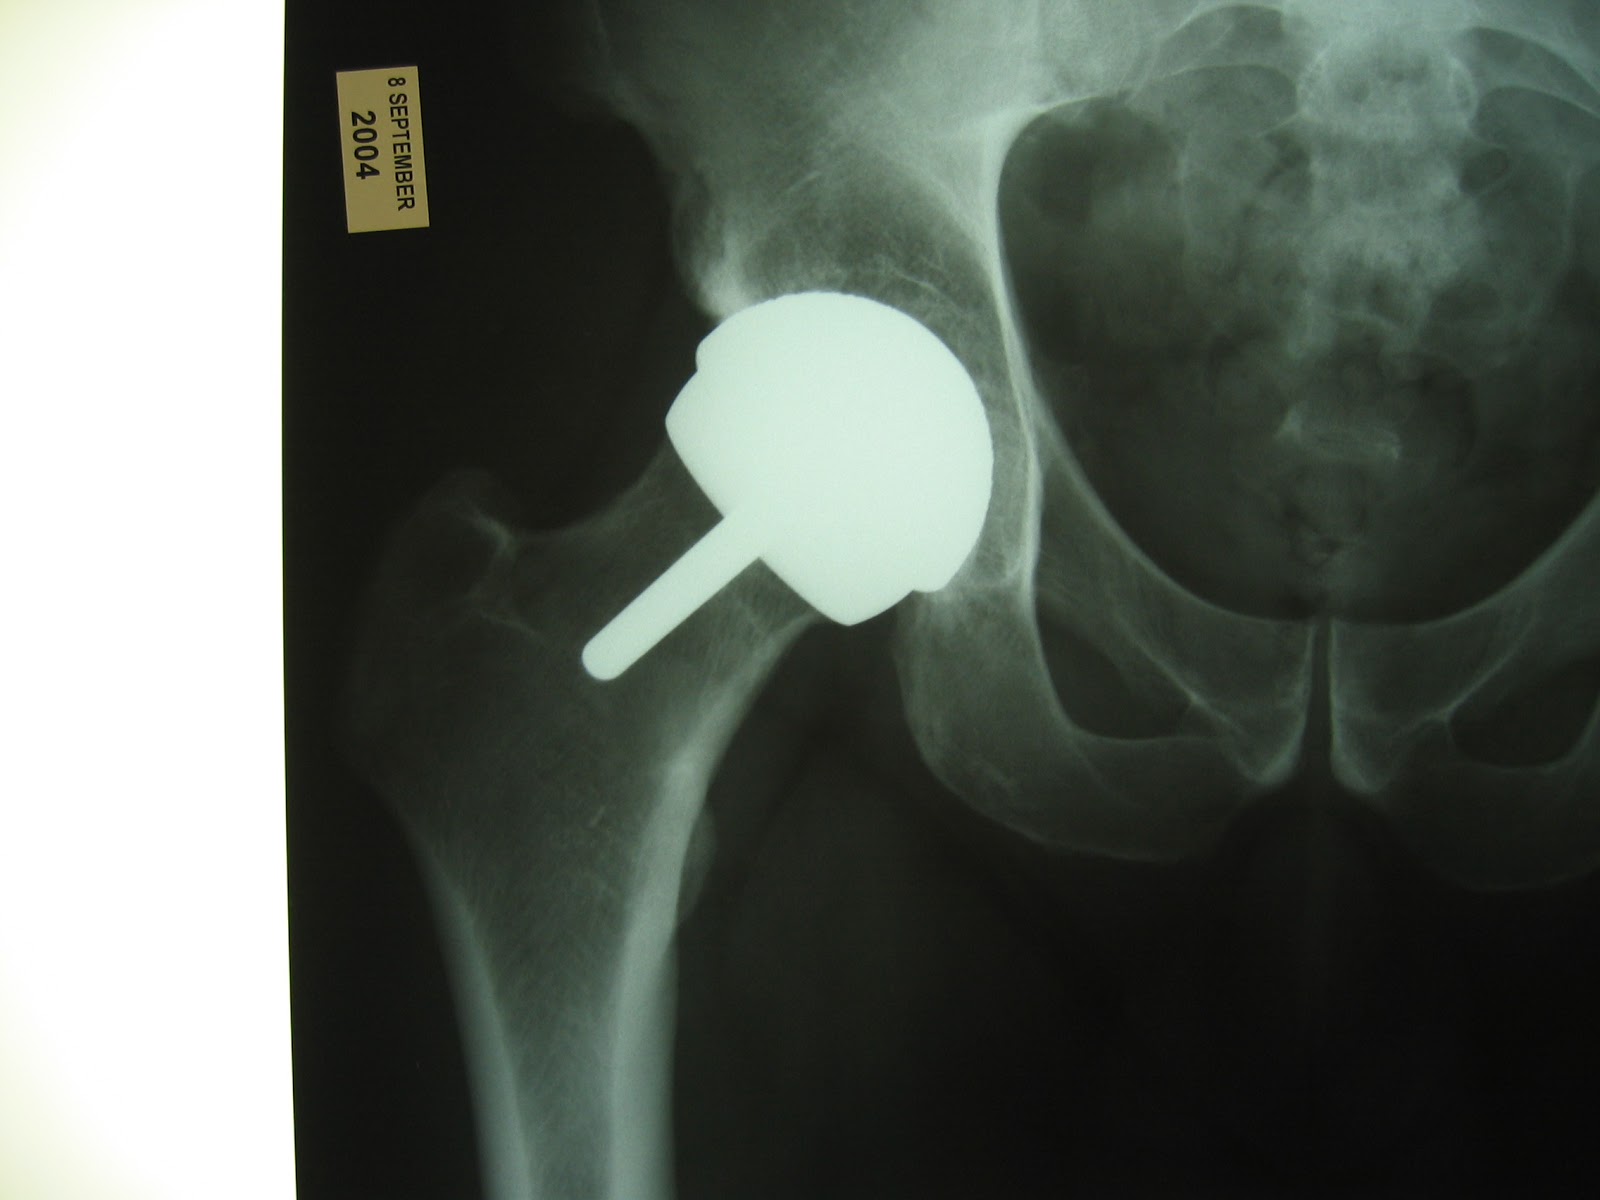

From radiopaedia.org

Hip resurfacing arthroplasty Image Hip Resurfacing Blog — my hip resurfacing is still great and i never had problems with it. Hip replacement vs hip resurfacing share. Once the surgical site has healed,. — hip resurfacing is surgery to treat chronic hip pain due to arthritis and other hip conditions. Stephen sizer, do february 6th, 2024. in a traditional total hip replacement, the head. Hip Resurfacing Blog.